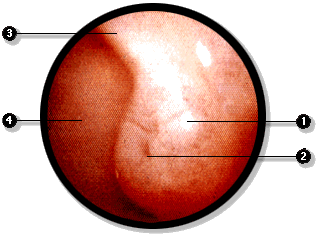

Mediante la endoscopía es posible examinar directamente la mucosa duodenal y observar, al nivel de la segunda porción del duodeno, la papila duodenal mayor, por donde se vierten las secreciones biliar y pancreática. Estas secreciones fluyen de los conductos colédoco y pancreático principal, los cuales desembocan juntos a nivel de esta papila.